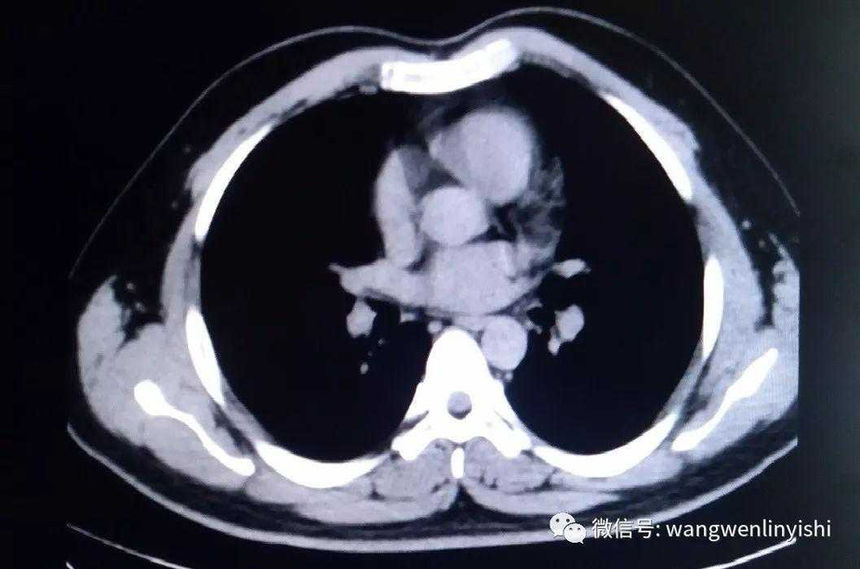

The upper part of the patient’s chest wall is protruded as a whole, coupled with depressions in the central and lower regions, presenting a classic example of Wenlin chest.

Wenlin chest is a distinctive chest wall deformity that was often mistakenly identified as pectus carinatum in the past. However, unlike PC, which is characterized by a single protrusion, Wenlin chest involves both protrusions and depressions, classifying it as a kind of complex chest wall deformities. This malformation can not be corrected by traditional surgeries that work for PC. Notably, the depression in Wenlin chest is only apparent in comparison to the protrusion of the upper chest wall, without significantly compressing the patient’s heart.